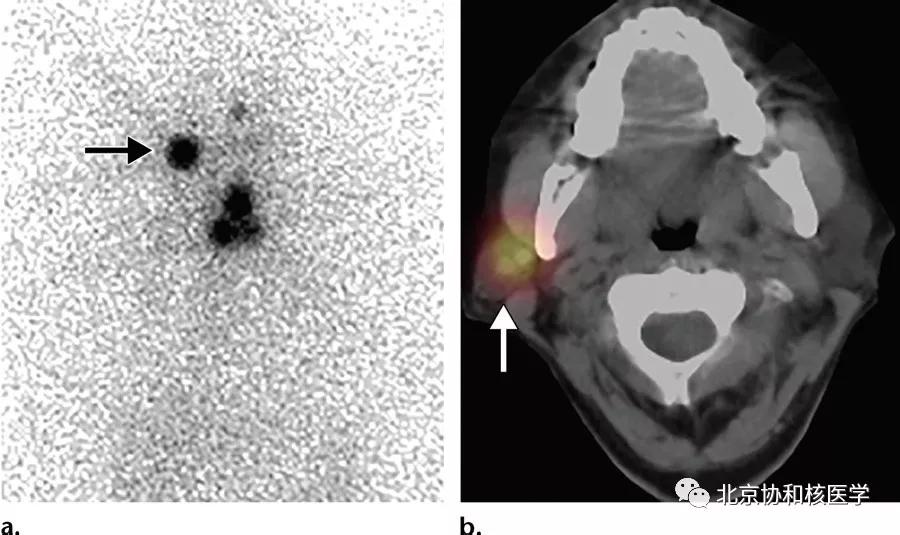

63岁女性,甲状腺乳头状癌甲状腺全切除术后,碘131治疗后,除颈部残余甲状腺外,碘扫见右侧腮腺软组织密度结节,摄取明显增高,穿刺活检提示腮腺良性肿瘤[2]: